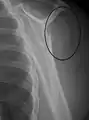

A fracture of the greater tuberosity as seen on AP X ray

A fracture of the greater tuberosity of the humerus